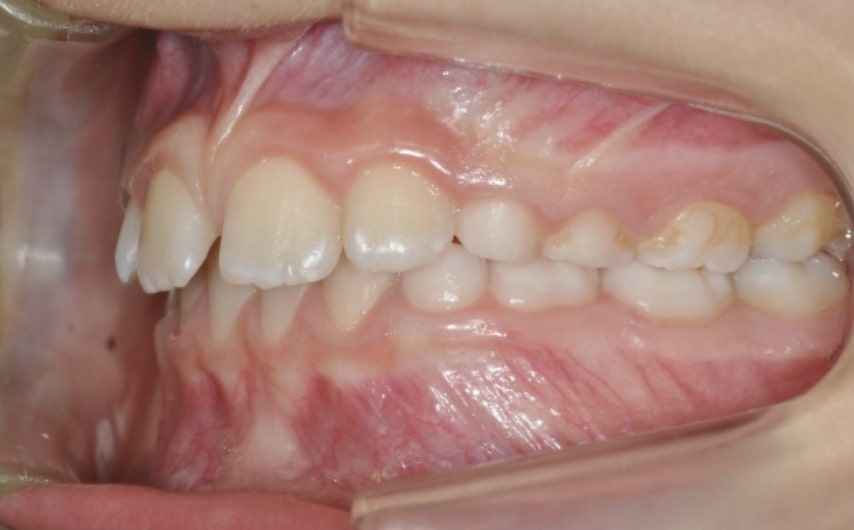

Malocclusion A6 Correction of Mandibular Retrusion in Growth phase patient | Skeletal Class II | Class II Division 1 malocclusion | Deep bite | Mixed dentition

Clinical examination and diagnosis

DENTAL:

• Molar and Canine class 2 on the right side – Molar and Canine clss 1 on the left side

• Increased Overjet

• DeepBite

• Reduced Transversal Diameters

• Deviated Lower Midline 2 mm to the Right